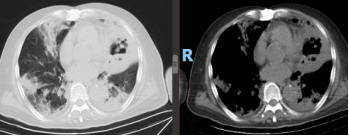

患者治疗10天后,复查炎症指标和胸部CT。

胸部CT复查结果: 双肺多发团片影,左肺内病灶可见空洞形成,双侧胸腔积液。